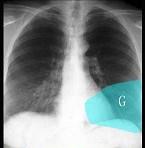

问题 如图所示正常胸部X线影像图像上,该英文字母所代表的肺段为 ( )

选项 A.内基底段 B.前基底段 C.外基底段 D.后基底段 E.背段

答案 B